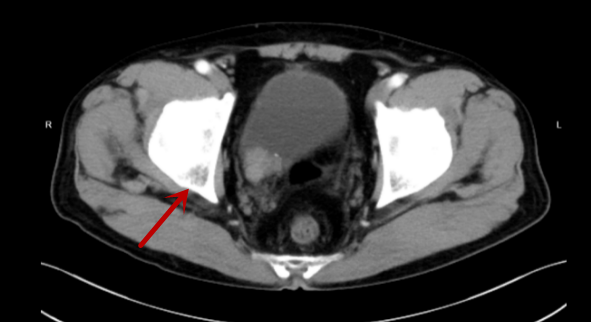

67岁的曾伯在外院体检时发现膀胱内有肿物,来我院门诊行CT检查提示右侧输尿管下段及膀胱右后壁占位,伴右肾大量积液。进一步膀胱镜检查可见膀胱右侧壁见肿物,大小约4*4cm,呈菜花状,活检结果提示尿路上皮癌,泌尿外科医生诊断考虑为输尿管恶性肿瘤合并侵犯膀胱。

CT检查提示患者右肾积液